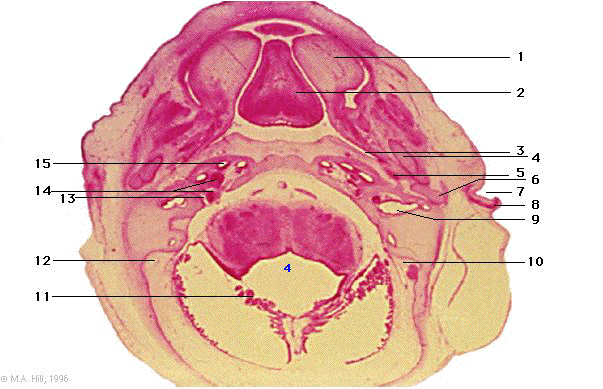

1 |

palatine shelf |

2 |

tongue |

3 |

pharyngo-tympanic tube |

4 |

Meckel's cartilage |

5 |

tensor tympani |

6 |

incus |

7 |

external auditory meatus |

8 |

auricle |

9 |

utricle |

10 |

endolymphatic sac |

11 |

choroid plexus |

12 |

sigmoid sinus |

13 |

internal auditory meatus |

14 |

vestibular and spiral ganglia (VIII) |

15 |

cochlea |